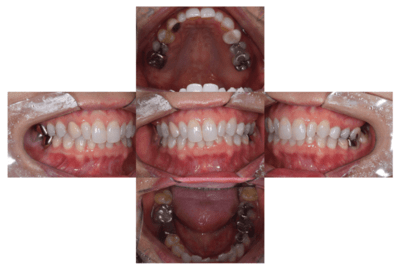

初診時の口腔内

説明:

初診時の口腔内です。かぶせ物があり、一見虫歯とはわからないです。